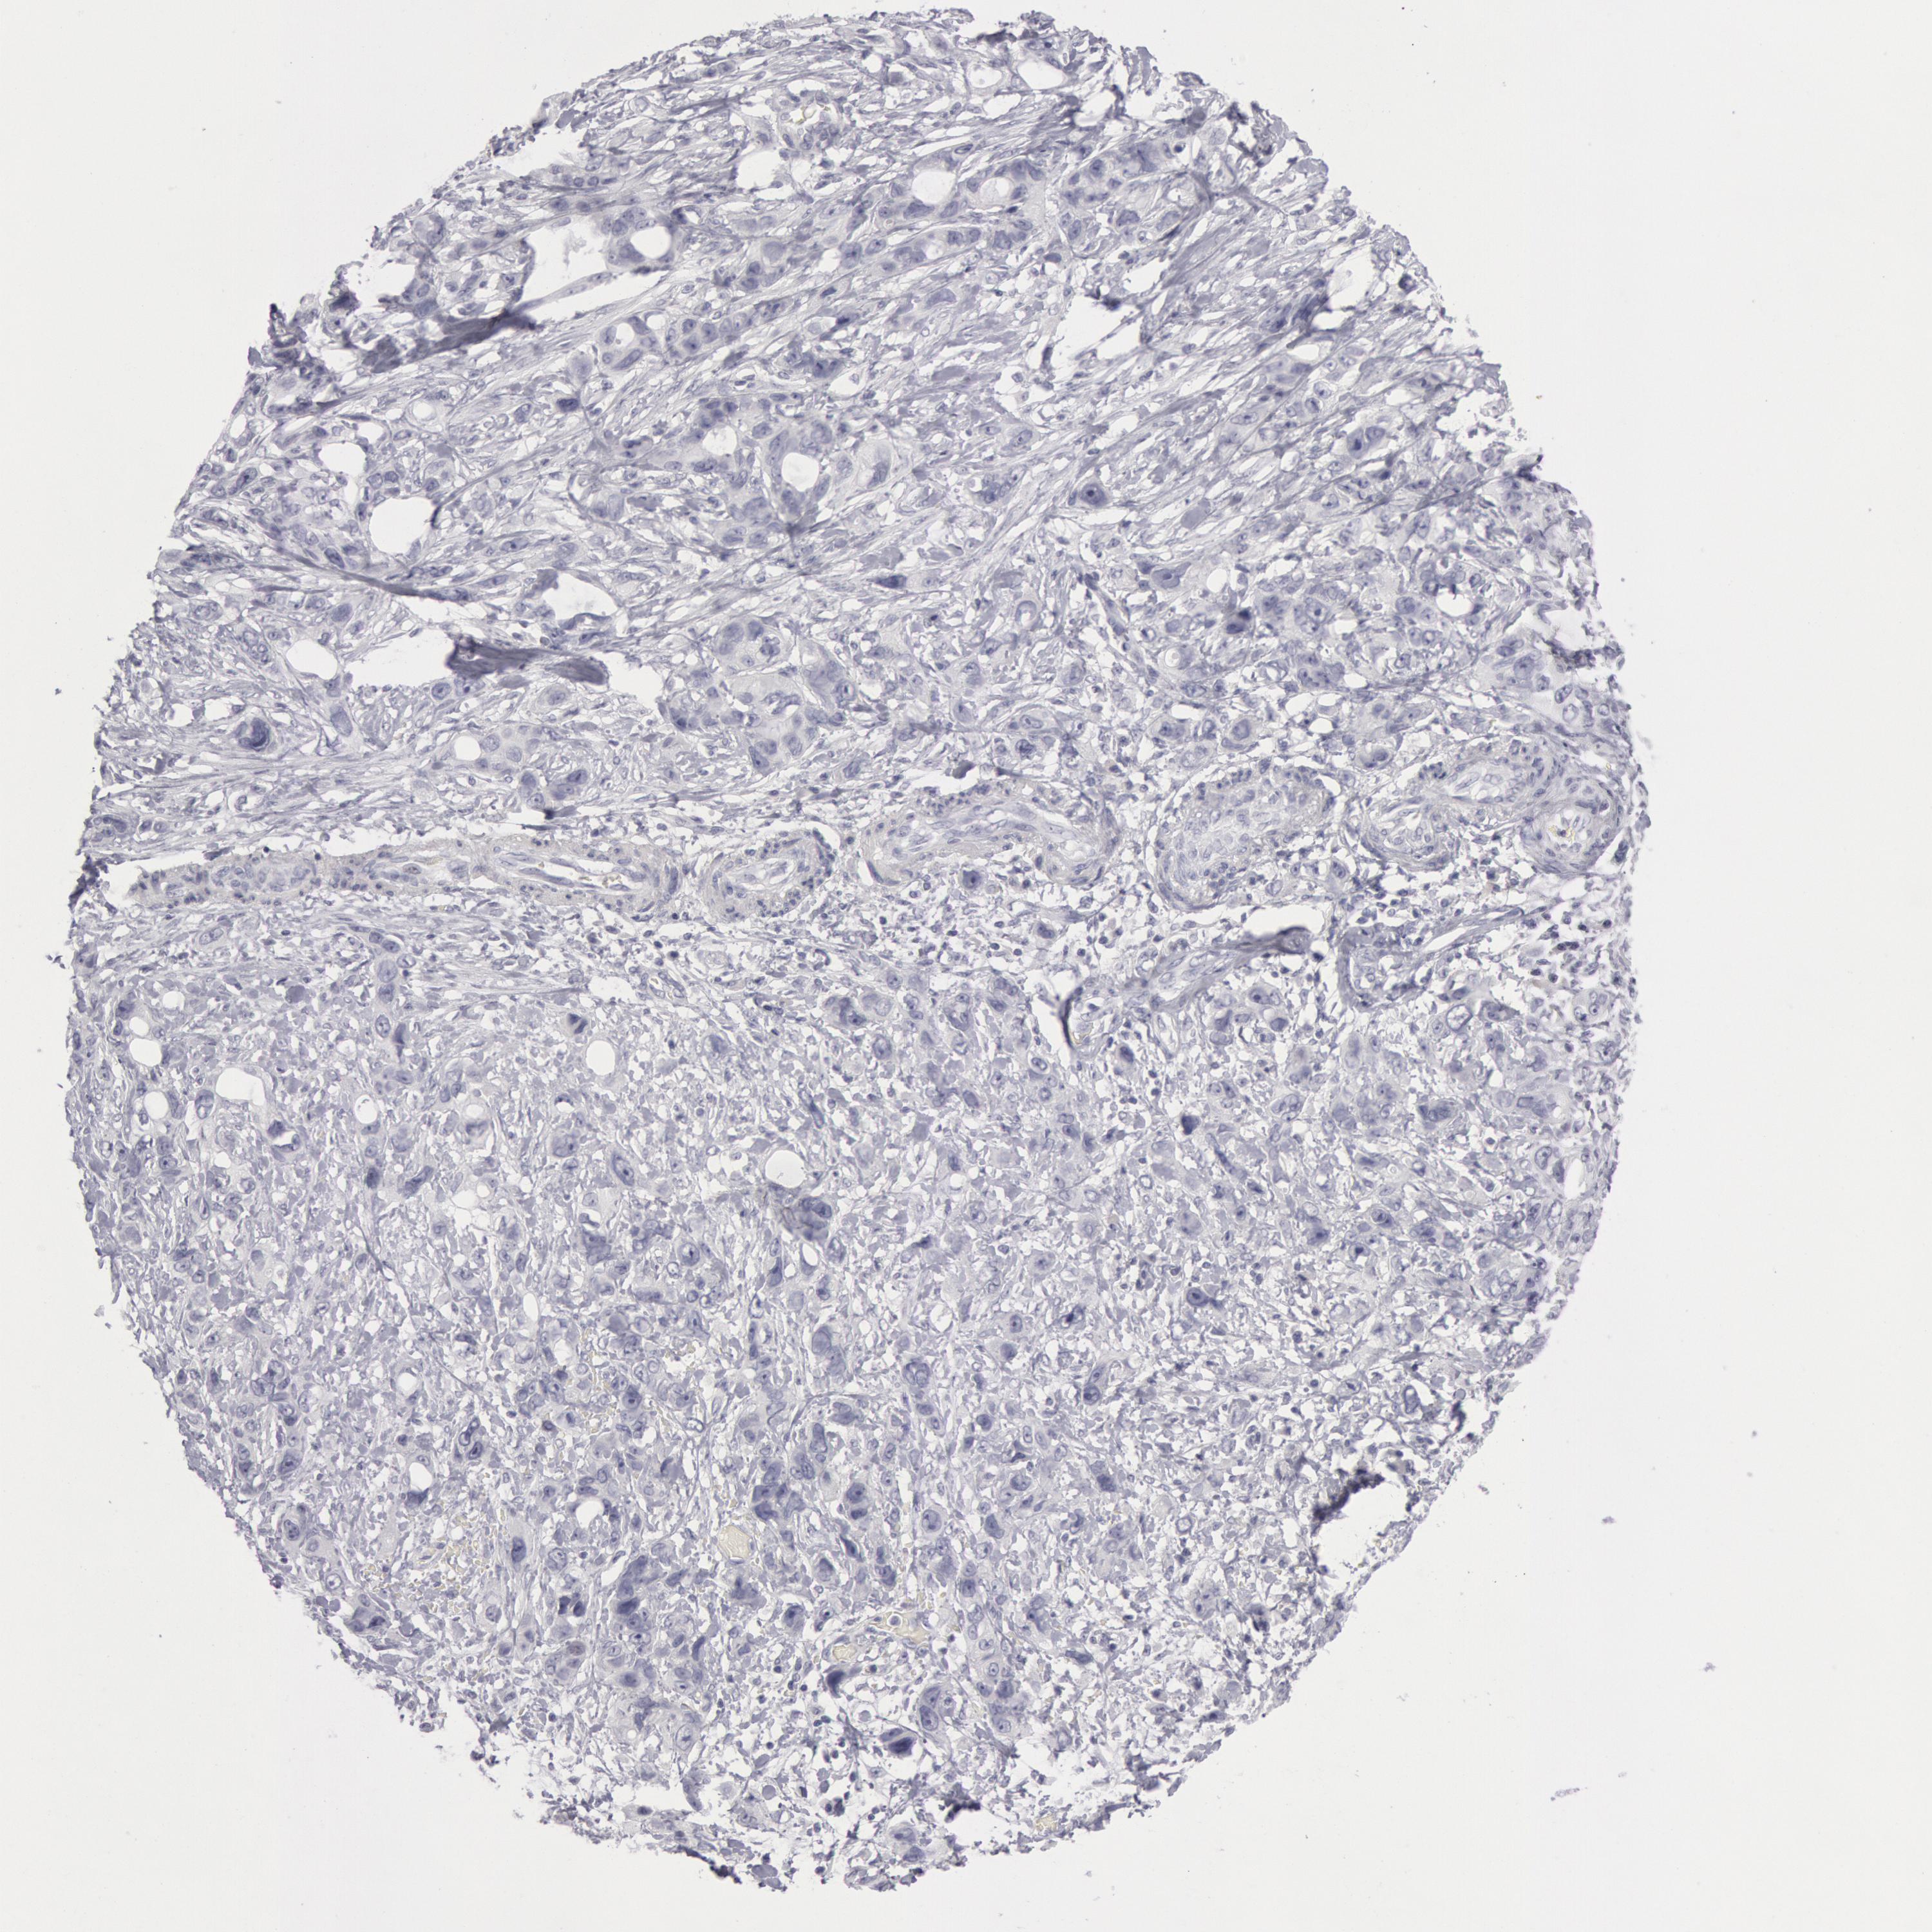

STOMACH CANCER - Protein expressioni

A mouse-over function shows sample information and annotation data. Click on an image to view it in a full screen mode. Samples can be filtered based on level of antibody staining by selecting one or several of the following categories: high, medium, low and not detected. The assay and annotation is described here.

Note that samples used for immunohistochemistry by the Human Protein Atlas do not correspond to samples in the TCGA dataset.

Antibody stainingi

Antibody staining in the annotated cell types in the current human tissue is reported as not detected, low, medium, or high, based on conventional immunohistochemistry profiling in selected tissues. This score is based on the combination of the staining intensity and fraction of stained cells.

Each image is clickable and will lead to virtual microscopy that enables deeper exploration of all samples and also displays staining intensity scores, fraction scores and subcellular localization as well as patient and tissue information for each sample.

Antibody CAB000136

Staining

High

Medium

Low

Not detected

Intensity

Strong

Moderate

Weak

Negative

Quantity

>75%

75%-25%

<25%

None

Location

Nuclear

Cytoplasmic/membranous

Cytoplasmic/membranous,nuclear

Adenocarcinoma, NOS